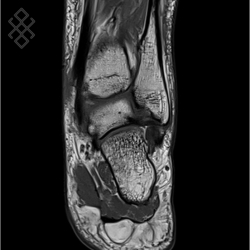

IRM de la Cheville

Vous entrez dans l'aimant, ouvert des 2 côtés, les pieds en premier et allongé sur le dos avec les bras le long du corps. Pour recueillir le signal et construire les images, vous aurez la cheville dans une antenne. Étant donné que cet examen est bruyant, vous aurez à votre disposition des tampons auriculaires pour atténuer le bruit de la machine.